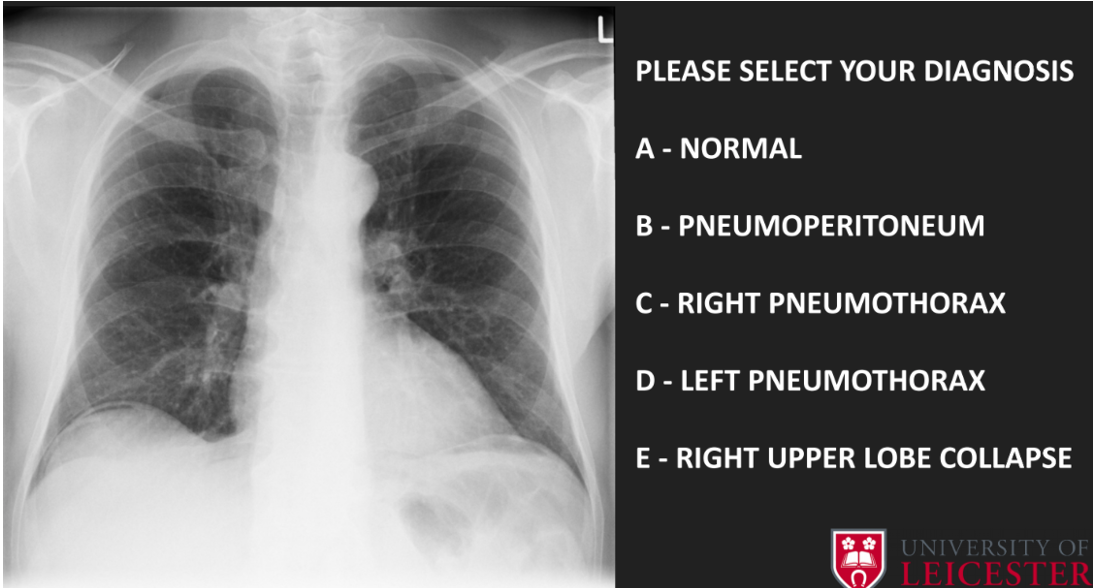

20

diagnosed

A

B- bilateral hilar lymphadenopathy

e.g. sarcoidosis

21

C- right upper lobe collapse

• Atelectasis- mediastinum pulled towards collapse